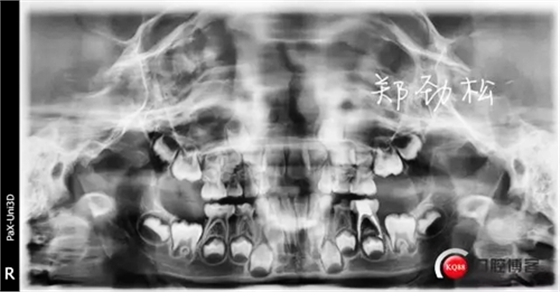

我的病例二 8E深齲導致的根尖炎

常規(guī)的開髓擴根后vitapex糊劑充填,可見近中根有明顯的糊劑超充。

一月后永久充填復查時可見炎癥明顯好轉,近中根超充的糊劑也吸收了,臨床癥狀也消失了。

我的病例三 7E牙髓炎